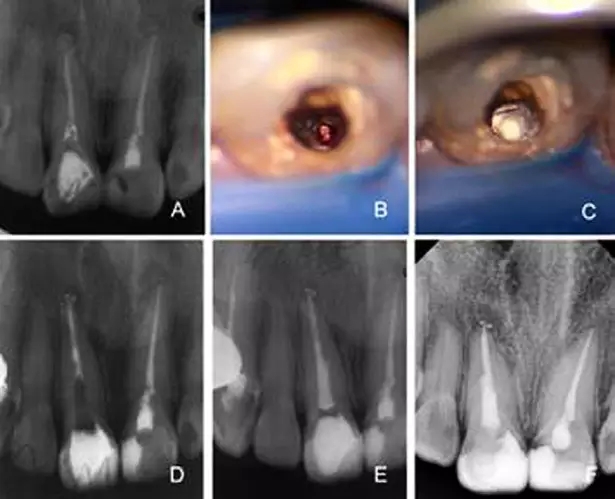

A:根管唇側(cè)穿孔,牙膠尖于穿孔處超填,根尖及近中側(cè)方有骨密度減低

影像 B:根管顯微鏡輔助下取出牙膠尖 C:MTA修補(bǔ)側(cè)穿孔 D:根管部分

充填 E:2月后根管及冠方充填 F:8個(gè)月后復(fù)查X線片可見(jiàn)暗影區(qū)減小

而在手術(shù)顯微鏡下術(shù)者可以對(duì)根管壁穿孔的位置、大小及形態(tài)等多個(gè)方面進(jìn)行仔細(xì)的定位和評(píng)價(jià)。對(duì)于根管穿孔的病例,新鮮的穿孔要即刻修補(bǔ),陳舊的穿孔用超聲器械對(duì)局部進(jìn)行清潔和預(yù)備,Ca(OH)2封藥一周后再進(jìn)行修補(bǔ)。治療中在建立直線通路后,顯微鏡下先用輸送器準(zhǔn)確放置修補(bǔ)材料,加壓壓實(shí)后充填,拍攝x線片,確認(rèn)形成良好的根尖屏障,再對(duì)剩余根管進(jìn)行常規(guī)充填,這方法可明顯提高根管壁穿孔非手術(shù)治療的成功率[10]。M TA是近年來(lái)逐漸被廣泛用于根管穿孔修補(bǔ)及根尖封閉的材料。M TA具有良好的封閉性、生物相容性,不溶于血液及組織液,并且具有x線阻射性,是一種較理想的根尖倒充填材料。顯微鏡下使用MTA修補(bǔ)根管壁穿孔,患牙治療成功率可達(dá)86%[11、12]。